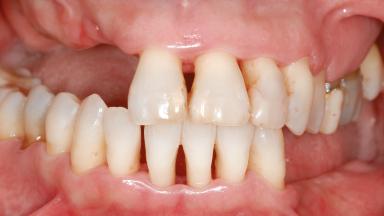

Shell Technique for Horizontal and Vertical Maxillary Bone Augmentation in a Partially Edentulous Patient with Aggressive Periodontal Disease

A 46-year-old woman was referred for treatment whose main complaints were mobility of her fixed partial dentures (right maxilla and left mandible) and periodontal bleeding during function. She also reported having taken systemic antibiotics to treat recurrent swelling in the area of the upper left molars. The patient had not seen a dentist for at least 2 years. She did not smoke and had no history of major systemic disease other than two minor orthopedic procedures some years back. The first-visit examination revealed poor plaque control, tooth mobility, periodontal disease, and a residual dentition widely associated with deep periodontal pockets.

Lip Line No exposure of papillae Exposure of papillae Full exposure of mucosa margin

Periodontal Phenotype Low-scalloped, thick Medium-scalloped, medium-thick High-scalloped, thin

Soft Tissue Anatomy Intact Defective

Bone Volume Horizontally and vertically sufficient Horizontally deficient Deficient vertically or deficient vertically AND horizontally